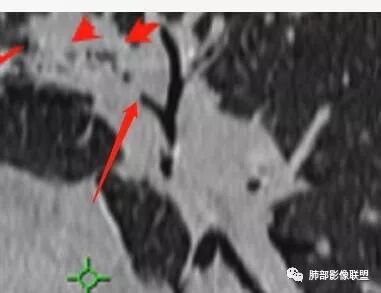

王秀仙:左肺上叶肿块,边缘平直收缩,周围可见长索条,轻度强化,密度不均可见低密度坏死,考虑结核。鉴别腺癌。Yiren  Sishui(厶水伊人):晨读:左肺上叶肿块,近胸膜侧光滑,提示符合淋巴回流病变,周围条索,符合肉芽肿性病变,环形强化,中心坏死,考虑结核可能luys:左肺上叶病变,沿支气管分布,边缘平直收缩,周围见长索条,轻度强化,伴边界可见低密度坏死灶。考虑特殊感染。灶内支气管中断,临床以咯血就诊,鉴别肿瘤。博麟:左上胸廓稍缩小,长条索病灶,冠状位似见支气管截断,坏死边界似乎欠清,猜个纤维条索基础上合并瘢痕癌红日东升:晨读:左上叶结块,前缘有粗大索条向前延伸,邻近前联合线明显左移,提示收缩明显。结块边缘平直、收缩;增强结块及索条明显强化,内血管走行自然,坏死灶周围似见三层结构;考虑炎性病变。wonderful:肿块实性边缘光滑  考虑良性病变 合并咯血 。结核或曲霉玫:左肺上叶不规则形软组织密度肿块影,边界清晰,期内密度不均匀,可见坏死,病灶向前呈条索状延伸,矢状位病灶形态欠规整,似有血管中断,考虑恶性病变可能,待除外结核?张帅:左肺上叶病变,病变周围平直,长毛刺,病灶内可见低密度区及支气管征,矢状位提示前段阻塞,病灶内气管不规则扩张,病灶周围有卫星灶,考虑良性病变:结核?我心飞翔:病灶边缘平直,中央可见坏死,周围磨玻璃边界欠清,考虑炎性病变张延军:左肺上叶尖后段肿块,边缘以平直为主,局部膨隆,内见片状坏死区,边界欠清,相应尖后段支气管闭塞,考虑占位并不张,腺癌?建议抗炎治疗后复查丽:左肺上叶病变,边缘平直,并可见长索条,增强后密度不均,可见坏死,首先考虑结核,但重建后支气管走形欠连续,似有截断,恶性待排毛勤香:左肺上叶病灶,边缘平直为主,周围索片影,增强强化不均匀,内有坏死,重建支气管走行欠规则,似有截断,老年男性,需排除恶性(鳞癌?)并阻塞性肺炎可能王萍:左肺上叶团片,大部分边缘平直、凹陷,周围见少许条片模糊影,增强内见坏死区,余区域较均质,其内支气管部分通畅,部分变窄。咯血病史,无发热,考虑肉芽肿性炎可能性大,结核或放线菌等,肿瘤待排THINKER:左上叶,占位,围绕尖后段支气管,U型凹丶平直,长索条,有轻强化及低密度,考虑良性的,首选OP,老年不发热丶咯血,鉴鳞癌、TB飞鹰行动:左肺病灶,有明显的收缩表现,增强后病灶内部可见低密度无强化区,病灶内支气管轻度扩张呈串珠状改变,支持炎性病变,结核可能性大。杨泽锋:支持炎性病变伴小脓腔形成,但不支持结核,因为病灶内可以可见血管影THINKER:问一下各位老师:这个给的强化,是肺动末期丶主动脉未期`延迟期?大雄:老年男性,左肺上叶前段条片状实变影伴周围长条索,境界清晰,边缘部分锐利光滑、部分毛糙,增强可见中央局部坏死,周围无强化区轻中度均匀强化,无钙化,无明显卫星灶,无胸膜明显牵拉凹陷。病灶整体收缩力有,张力不明显,肿瘤概率小。临床无明显急性感染症状,倾向于慢性增生性炎症,累及段支气管,引起了咯血。结核多见,但慢性结核肉芽肿一般强化没这么明显。OP不除外。老年男性如果有长期吸烟史,鳞癌不能完全排除,鳞癌的坏死强化都符合,鳞癌收缩力也不强,形态更是变化无常左手:老年男性,咯血,左肺上叶长条样结节,边缘见牵拉影,支气管堵塞,病灶内见坏死,坏死边缘偏清,考虑鳞癌,鉴别结核宇宙星空:支持恶性。鳞癌可能性大。支气管截断及空泡征

Shelia:考虑机化性肺炎伴小脓肿形成?炎性肌纤维母细胞瘤?鉴别癌食客:左肺上叶病灶,边缘平直,周围条片影,增强内见坏死区,内支气管部分通畅,咯血病史,无发热,考虑结核,肿瘤不除外。管洪林:左肺上叶尖后段病变,整体边缘平直,部分稍收缩,临近长索条影,胸膜缘可见轻度牵拉,增强后整体强化明显,其内可见低密度类圆形坏死区,边界清,首先考虑op并小脓肿形成,但部分层面显示小支气管受阻,是否层面原因?管洪林:若是支气管阻塞,鳞癌作为鉴别雪上一枝蒿(陈显静):他这个动脉期是不是不是很明显啊,觉得跟静脉期差不多,强化值也不好分辨?徐超:左肺上叶实变,边缘平直,周围无磨玻璃及卫星灶,病灶内坏死,强化后边界清楚,无壁结节,余病灶轻中度均匀强化(对比肌肉),增强后血管显影清楚自然,未见破坏边缘毛糙,血管旁条形无强化区(粘液?)整体符合炎性特点,炎性假瘤或op可能,伴小脓肿;结核放后面待排(结核病灶内血管完好,边缘清楚,且强化近中度,不是很合理,肉芽肿到也可以)。红日东升:平扫和强化窗宽窗位不一样良孑:左上实变,有平直及长毛刺,其内支气管牵拉性扩张,提示收缩力较强,无卫星灶,强化不支持TB,均匀强化,无分叶不支持鳞癌,影像上提示慢性进程,考虑OP并脓肿,鉴别炎肌母。

南边:应该是前段吧。前段的支气管怎么样?

宇宙星空:看远端的话是狭窄了吧,但是近端明显是截断啊,远端的是肺泡腔?

南边:坏死如何?

宇宙星空:是坏死吧,内壁边界不清

张延军:坏死边界清

宇宙星空:坏死明显